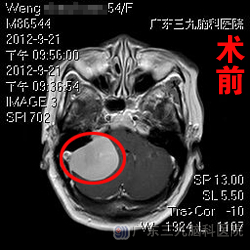

相关头部检查提示:右侧桥小脑角区占位性病变,考虑为脑膜瘤(肿瘤较大,约为46.3mm×33.6mm×39.3mm);幕上梗阻性脑积水。在明确手术指证,完善术前检查后,9月25日,由神经外七科吾太华主任主刀,翁老师在全麻下接受了右侧侧脑室外引流术+右侧桥小脑角区占位切除术。